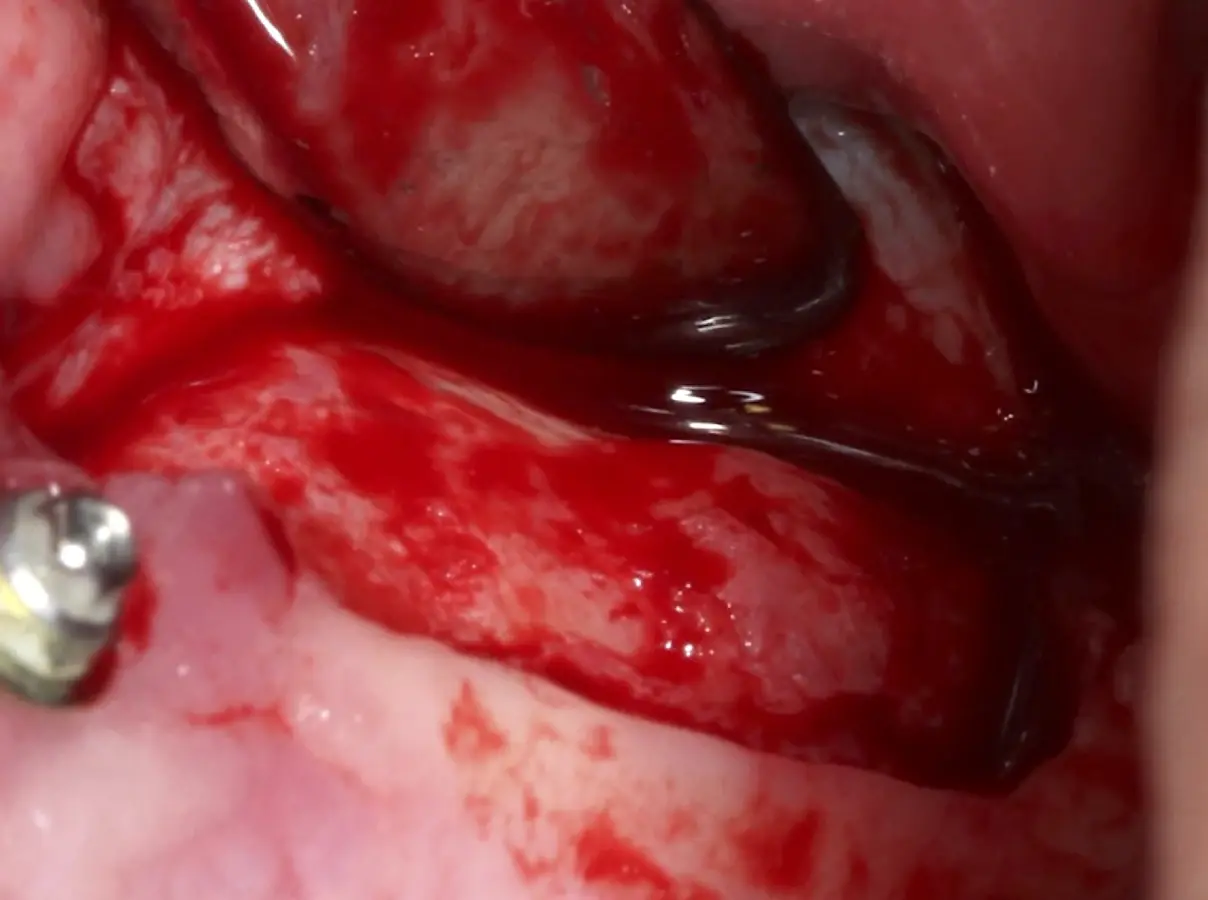

La técnica se inicia con la colocación de anestesia infiltrativa, posteriormente se realiza una incisión crestal o paracrestal con posibles liberantes verticales que deben de estar alejadas por lo menos 5 mm de los límites de la futura ventana y sobrepasar la línea mucogingival. Se realiza una elevación de colgajo, se inicia la antrostomía y antroplastía. Para ello, se emplea el inserto redondo diamantado de corte al momento de delimitar los bordes de la ventana de acceso. Luego se cambia al inserto aserrado liso de calibre fino con superficie diamantada, para profundizar y eliminar el hueso en el contorno de la ventana. Una vez que se traslucen los tejidos, se puede optar por el retiro de la tapa ósea o el levantamiento de ésta junto con la membrana.

Se inicia la elevación de la membrana de Schneider con el inserto redondeado no cortante en forma de disco, empleando movimientos suaves. El levantamiento puede complementarse con elevadores convencionales, siguiendo la dirección mesiodistal. La fase de desprendimiento inicia con el piso y sigue hacia la pared mesial para terminar, y de ser necesario, hacia la pared posterior. Existen diversos insertos con angulaciones y longitudes para mayor accesibilidad16 (Figura 1).

Una vez elevado el piso sinusal según la planificación se realiza la evaluación clínica de la integridad de la membrana y de posibles desgarros a través de la maniobra de Valsalva.24 Consiste en pedir al paciente que respire profundamente y retenga el aire, cerrar la boca, apretar la nariz con los dedos y forzar la salida de aire. Al final de la prueba, es necesario mantener la presión entre 10 a 15 segundos. Se identificará la movilidad de la membrana y la ausencia de burbujas de aire para corroborar que no hay perforaciones. Dependiendo de la decisión clínica se puede optar por adicionar en la superficie de la membrana de Schneider membranas de colágeno o de plasma rico en fibrina (PRF) para dar mayor soporte durante la inserción del biomaterial de relleno óseo (Figura 10).